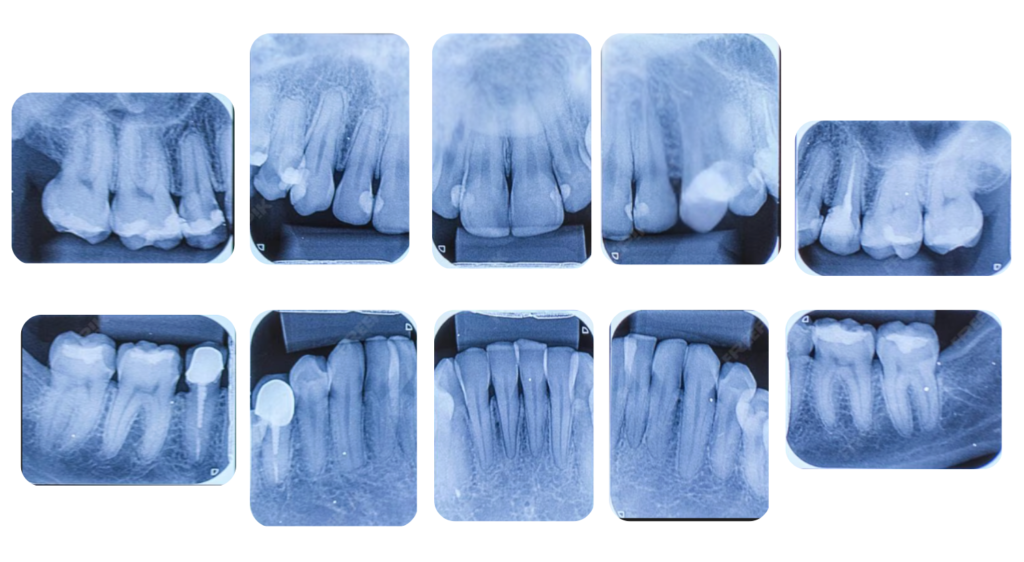

🦷 パノラマレントゲン・

10枚法X線写真(レントゲン)

パノラマレントゲン

デンタルX線写真10枚法

歯周病の治療計画を立てる上で、レントゲン撮影は目に見えない「歯を支える骨」の状態を知るために欠かせない検査です。

当院では、主に「パノラマレントゲン」と「デンタルX線写真(10枚法など)」の2種類を撮影します。

2. デンタルX線写真(10枚法)

デンタルX線写真は、特定の歯と、その周りの小さな範囲を一点集中で拡大して撮影するものです。

こちらは、歯周病が進行し、骨が溶けている箇所をより精密に確認するために行います。パノラマ写真では見逃しがちな、ごく初期の骨の変化や、歯の根っこの先の状態、歯石の付着状況などを詳細に分析できます。

歯一本一本の正確な診断と、歯周病治療の成功に直結する細かい情報の取得を可能にします。

このように、広範囲を把握する「パノラマ」と、詳細を分析する「デンタル」を組み合わせることで、歯周病の状態を診断し、最適な治療計画をご提案しています。